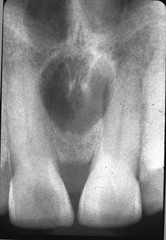

Nasopalatine Canal Cyst

Front

Located between max. centrals or around incisive foramen (occlusal radiograph to see)

Back